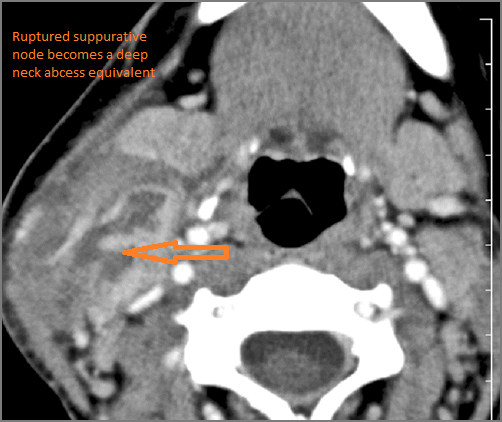

9 month old male presenting to the emergency room with poor feeding, fever, respiratory distress and possible retropharyngeal abscess or suppurative retropharyngeal adenitis.Exam

There is suppurative retropharyngeal lymphadenopathy. |

Yes | NA |

If there is suppurative retropharyngeal adenopathy what is the maximum short axis dimension of the largest suppurative node. Measurement |

< 2cm | NA |

There is edema/abscess within the adjacent parapharyngeal and retropharyngeal spaces. |

Pharyngitis with suppurative retropharyngeal adenitis.